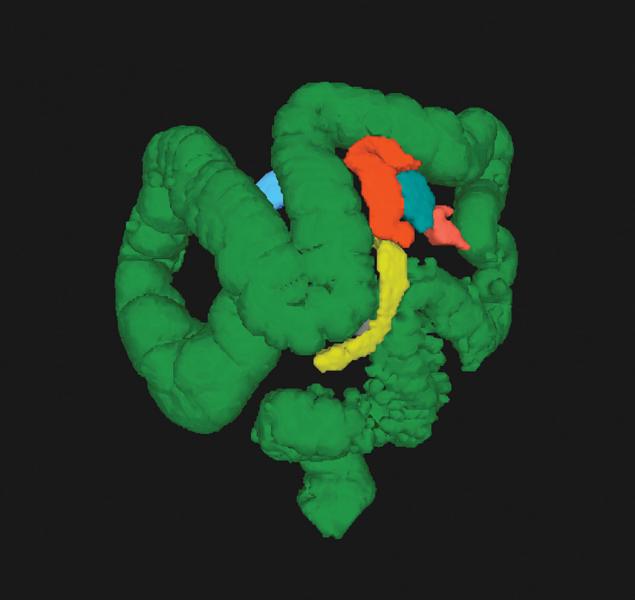

Computed tomography colonography (CTC), also known as virtual colonoscopy, offers a noninvasive alternative to ...